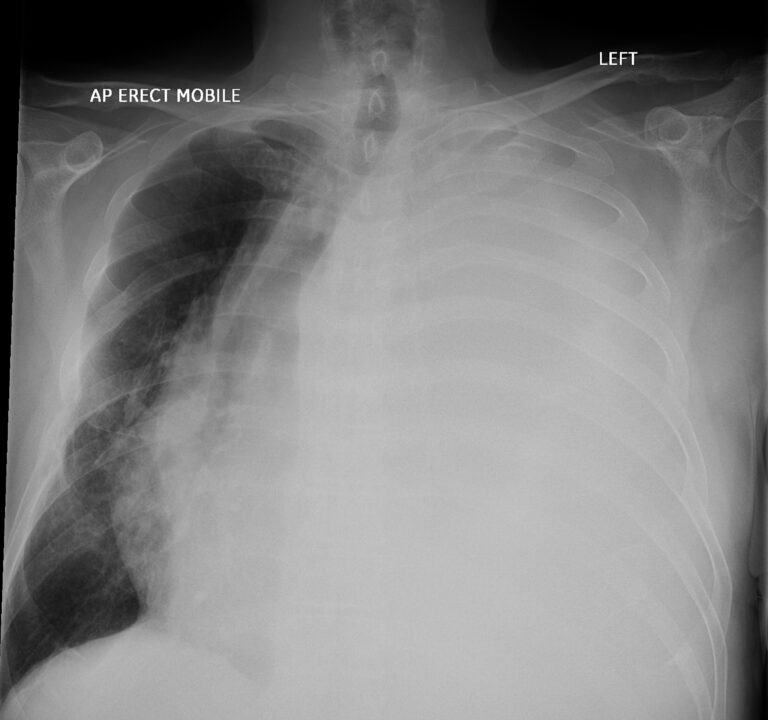

Have a look at the Chest X-ray below:

AP view of a Chest X-Ray of a male in his 70s presenting with breathlessness

The X-ray is clearly not normal. The left side is completely opacified: this can be termed a white-out. By looking at the mediastinum we can try and work out the cause.